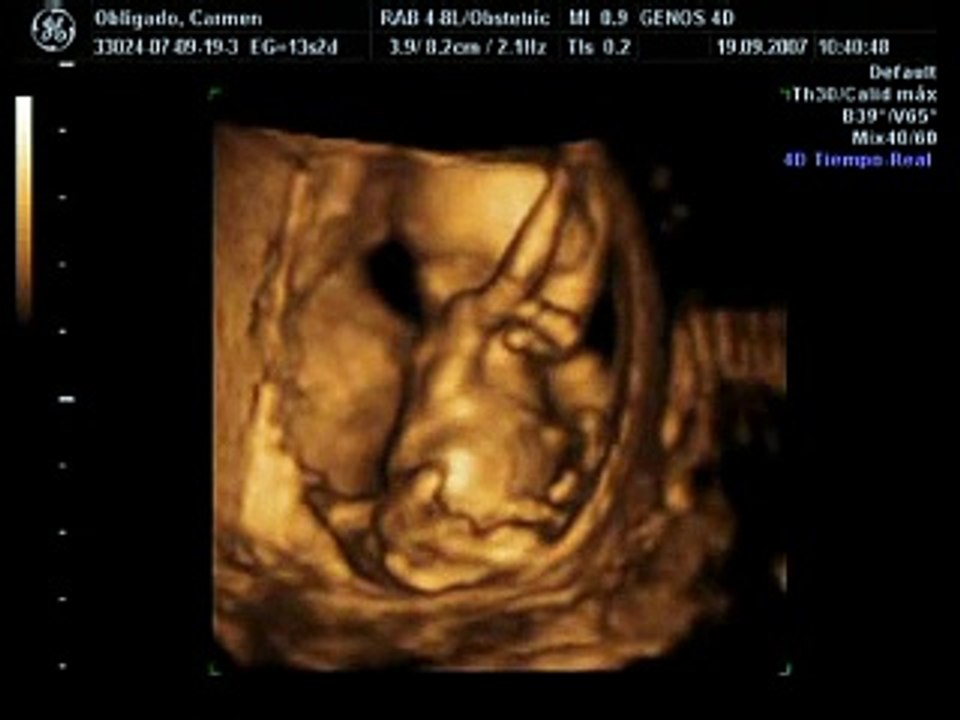

الجنين الاسبوع الثالث عشر من الحمل

الجنين الاسبوع الثالث عشر من الحمل. نصائح في الاسبوع الثالث عشر من الحمل. شكل الجنين في الاسبوع الثالث عشر بالسونار الأسبوع الثالث عشر من الحمل أي شهر. تستطيع كل سيدة أن تحتسب أشهر حملها بكل سهولة عن طريق معرفتها لأول يوم لآخر دورة لها في أشهر الحمل مقسمة إلى ثلاث مراحل ويعتبر الأسبوع.

الآن تقل أعراض الغثيان بشكل كبير لذلك عليك الانتباه إلى تعويض ما ينقصك من الغذاء مع الاهتمام بتنوع العناصر الغذائية اللازمة. يمكن أن يبلغ طول الجنين في الأسبوع الثالث عشر من الحمل حوال 9 5 سنتيمترا ويصل وزنه إلى ما يقارب 35 جراما كما أن حجم الطفل قد يساوي حجم حبة الخوه ويصبح رأسه أكثر توزنا ويشكل حوالي ثلث حجم جسمه الكلي. تكو ن الجنين الأسبوع 13 من.

تعرفي على مراحل نمو الجنين الاسبوع الثالث عشر من الحمل مر أكثر من شهري ونصف من الحمل هل شعرتي بهم. يقول الخبراء إن كل جنين يتكو ن بطريقة مختلفة حتى وهو داخل الرحم. تنتظر الأم الحامل جنينها بفارغ الصبر وتطرح الكثير من التساؤلات حول شكله وحجمه وطوله حيث إن نموه يستمر في كل أسبوع يمضيه داخل رحمها ووصولا إلى الشهر الرابع من الحمل يصل وزن.